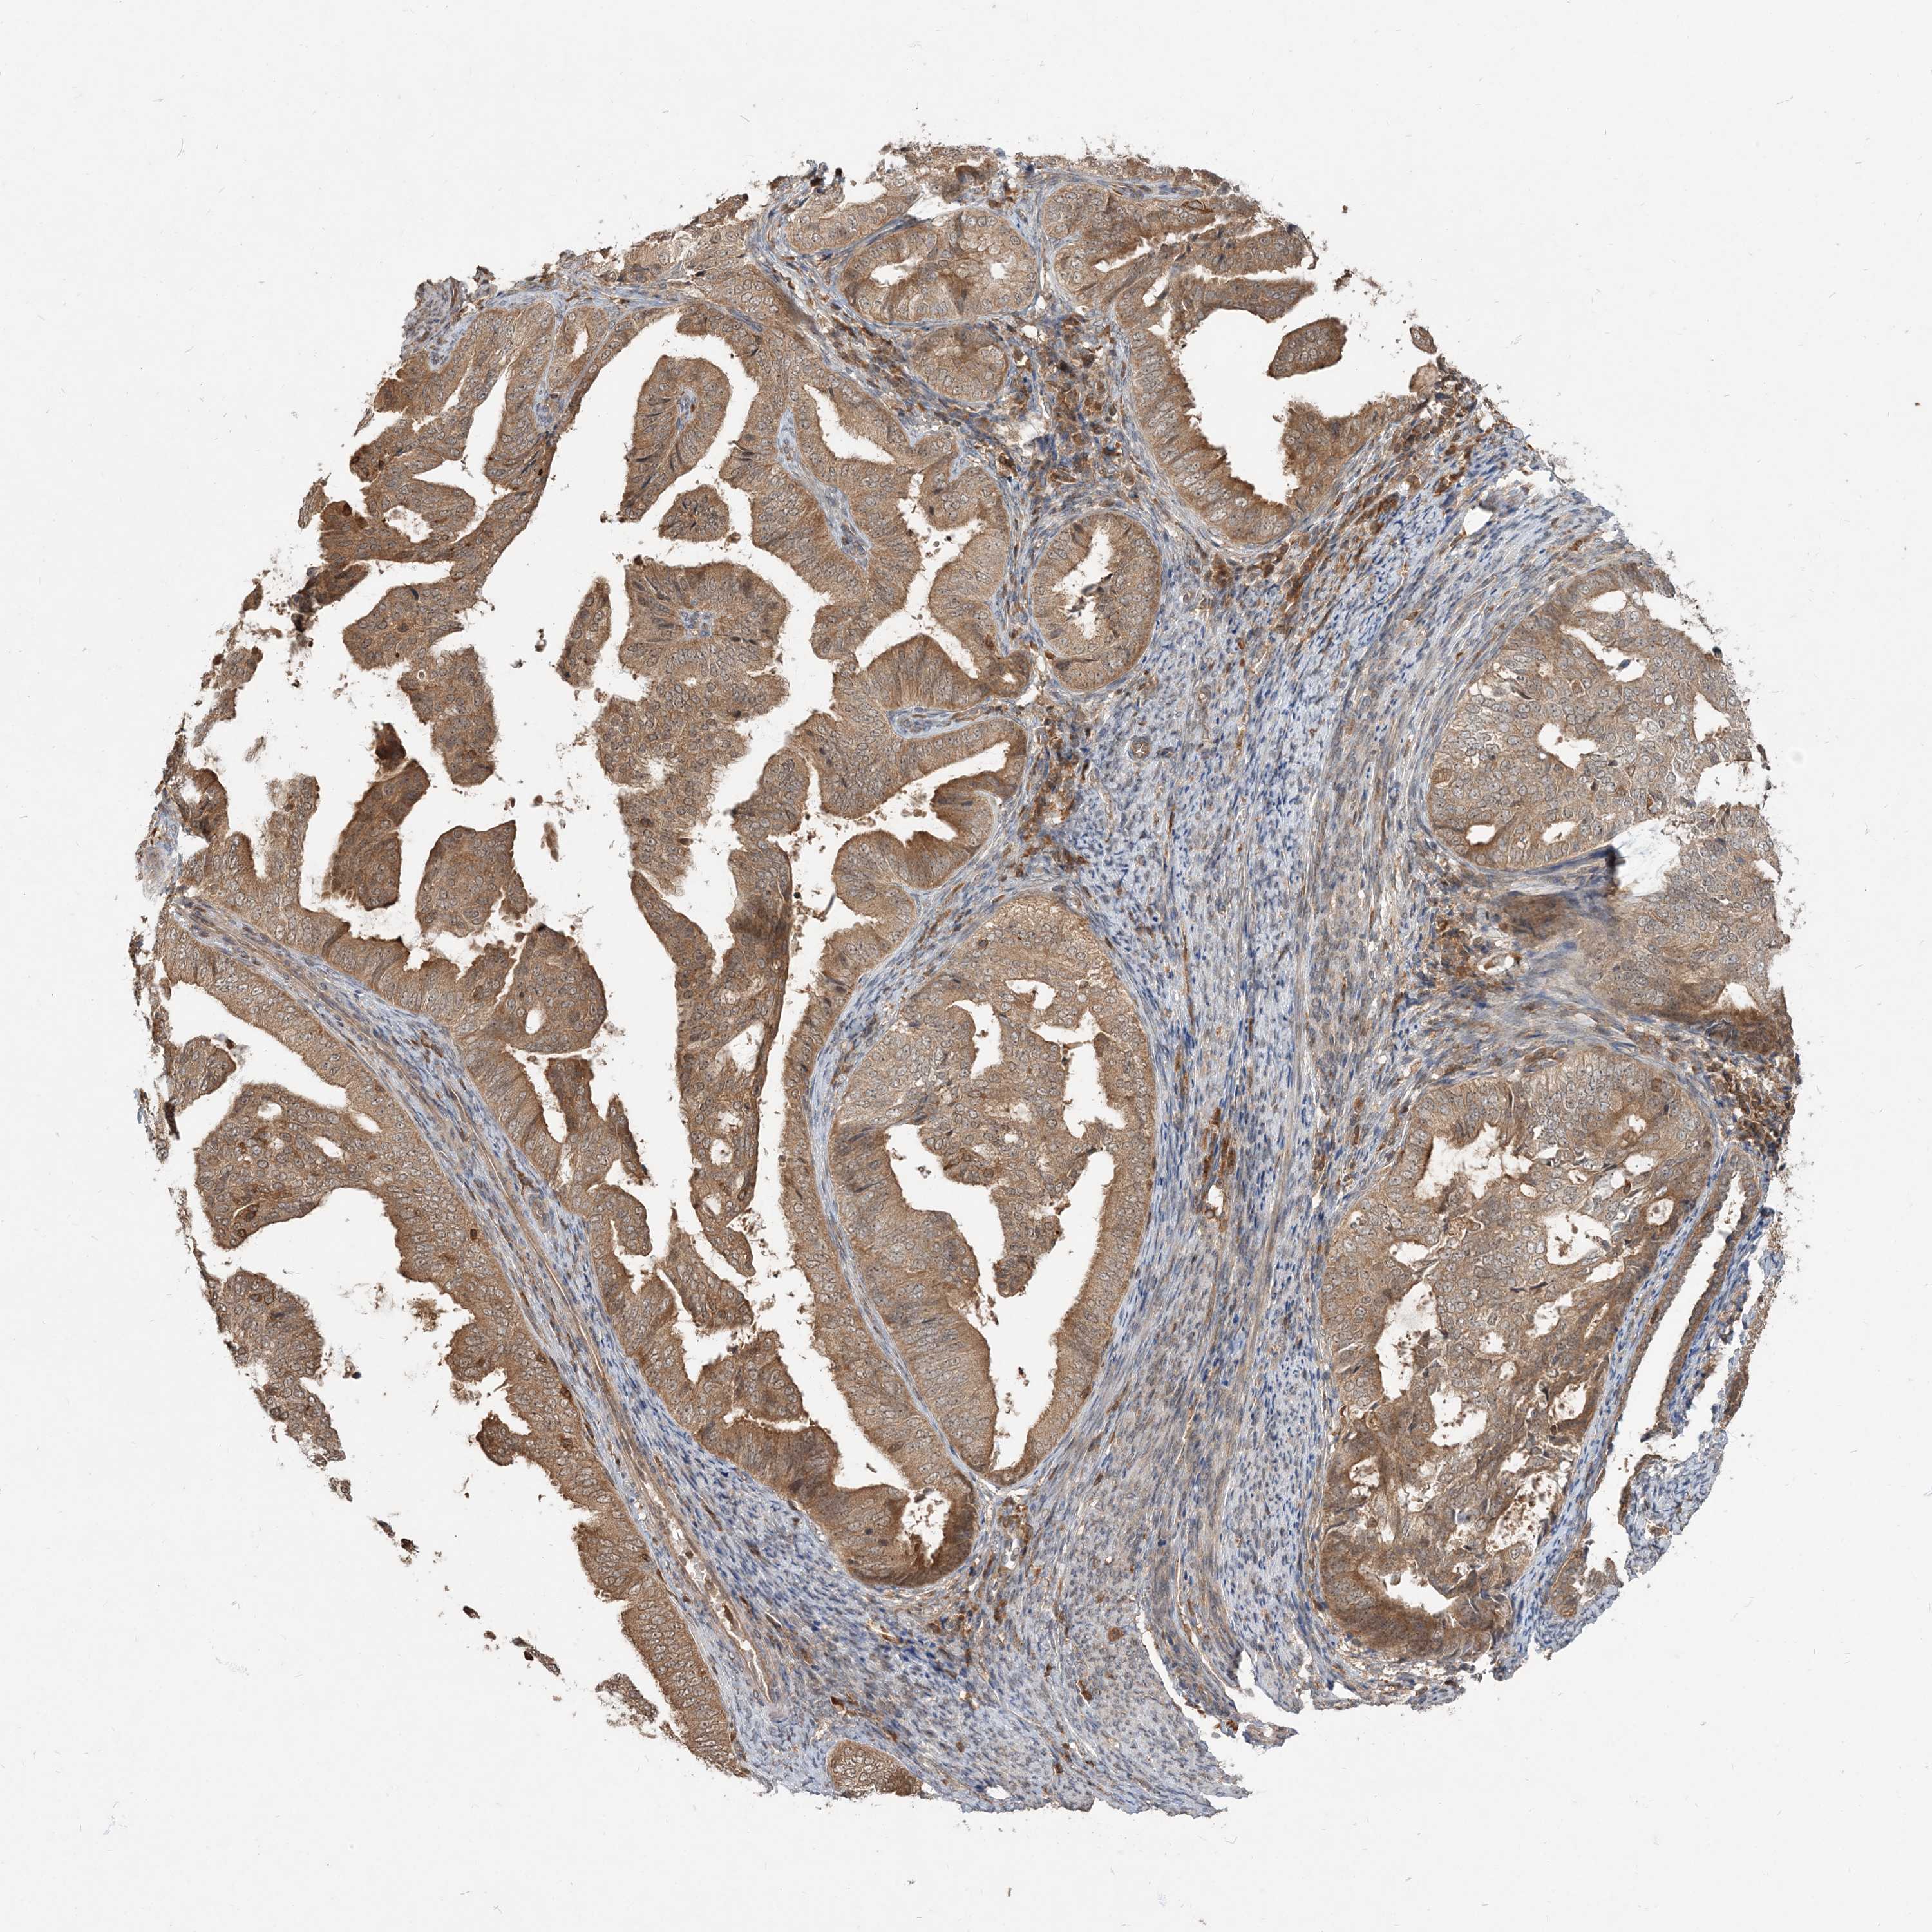

ENDOMETRIAL CANCER - Protein expressioni

A mouse-over function shows sample information and annotation data. Click on an image to view it in a full screen mode. Samples can be filtered based on level of antibody staining by selecting one or several of the following categories: high, medium, low and not detected. The assay and annotation is described here.

Note that samples used for immunohistochemistry by the Human Protein Atlas do not correspond to samples in the TCGA dataset.

Antibody stainingi

Antibody staining in the annotated cell types in the current human tissue is reported as not detected, low, medium, or high, based on conventional immunohistochemistry profiling in selected tissues. This score is based on the combination of the staining intensity and fraction of stained cells.

Each image is clickable and will lead to virtual microscopy that enables deeper exploration of all samples and also displays staining intensity scores, fraction scores and subcellular localization as well as patient and tissue information for each sample.

Antibody HPA076632

Antibody CAB037112

Staining

High

Medium

Low

Not detected

Intensity

Strong

Moderate

Weak

Negative

Quantity

>75%

75%-25%

<25%

None

Location

Nuclear

Cytoplasmic/membranous

Cytoplasmic/membranous,nuclear

Adenocarcinoma, NOS